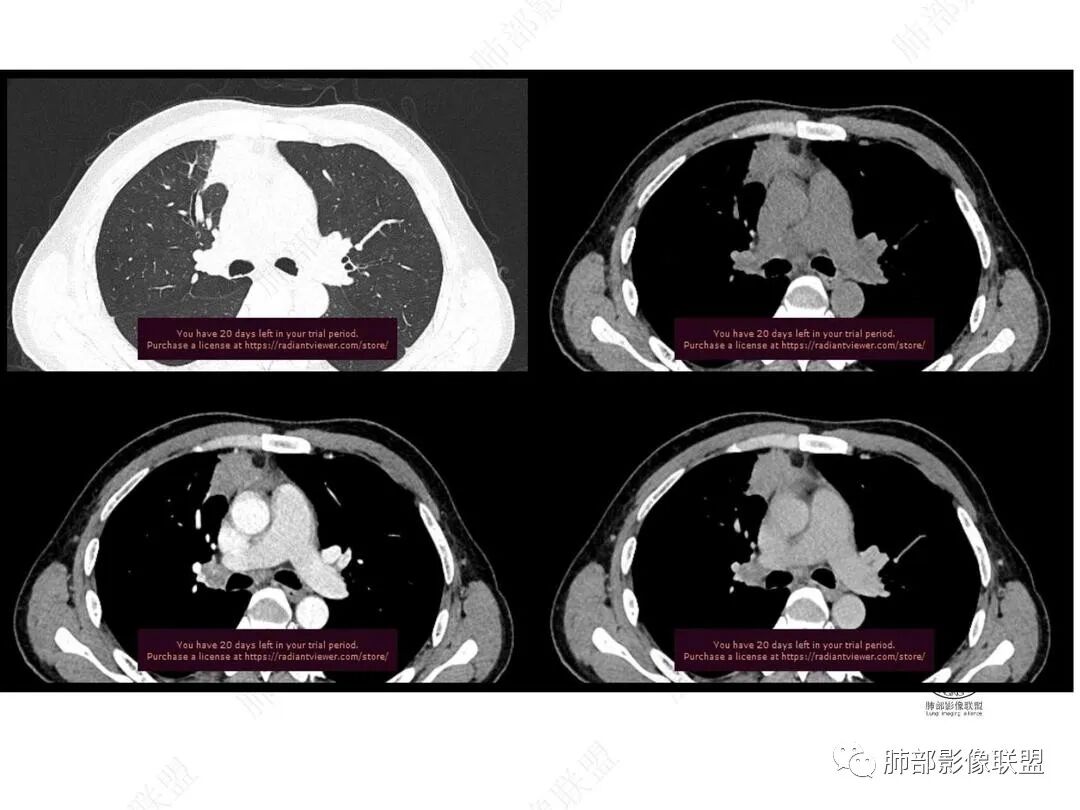

2.右肺上叶纵隔旁新发实性密度病灶,密度均匀,轻度强化,未见空洞、液化坏死及钙化,血管穿行自如,支气管进入后狭窄截止。灶周磨玻璃影边界不清,病灶未见明显分叶毛刺,平直、轻度收缩、周围偶见结节影,但未见树芽征。注意纵隔胸膜侵入或突入比较明确。纵隔淋巴结轻度增大。

3.右肺容易想到的病变有慢性炎症、IGg4相关、新生物(炎性肌纤维母细胞瘤、腺癌等)。但病灶侵入纵隔胸膜应当更符合恶性肿瘤。病程进展及强化等影像特点不支持继发性肺结核。

4.肝脏病灶没有假包膜,没有动脉早期强化,没有肝硬化,未见扩张胆管,未见环形强化,也未显示靶征,缺乏肝细胞肝癌、胆管细胞癌、转移癌或肝脓肿特征。

但回顾性分析,如此少血供确实可以符合淋巴瘤,如果密度更均匀一点的话,这是我们有所忽略的地方。

5.淋巴瘤可以解释影像改变,但仅凭影像及临床很难想到它是霍奇金!结外病变主攻方向以肝组织、肺组织为主,还突破胸膜?